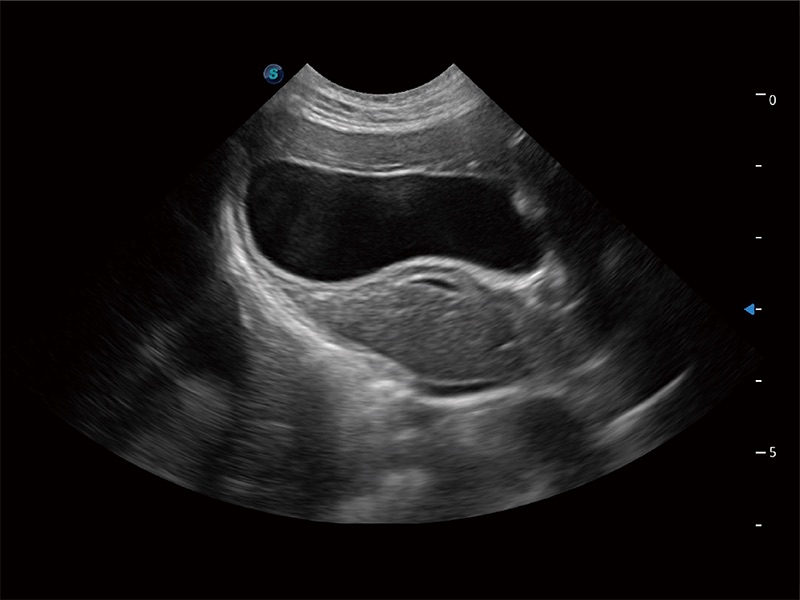

高性能和先進的臨床應用工具可以為動物醫(yī)生提供臨床信心。ProPet 80 搭載了先進的腹部和淺表應用工具,幫助醫(yī)生在日常臨床實踐中發(fā)揮前所未有的作用。

ProPet 80 專為動物醫(yī)生設計,對不同的動物體型和生理結(jié)構(gòu)作出了針對性的優(yōu)化。通過動物影像專用軟件,可滿足個性化的應用需求,幫助動物醫(yī)生獲得更精確的診斷數(shù)據(jù)。

ProPet 80 全新的動物超聲智能軟件和豐富的探頭群,為動物醫(yī)生提供了高清晰度和精細分辨率的圖像,無論在寵物、馬科、畜牧還是實驗室動物等應用中都可以輕松應對,為您的日常工作帶來滿意的體驗。